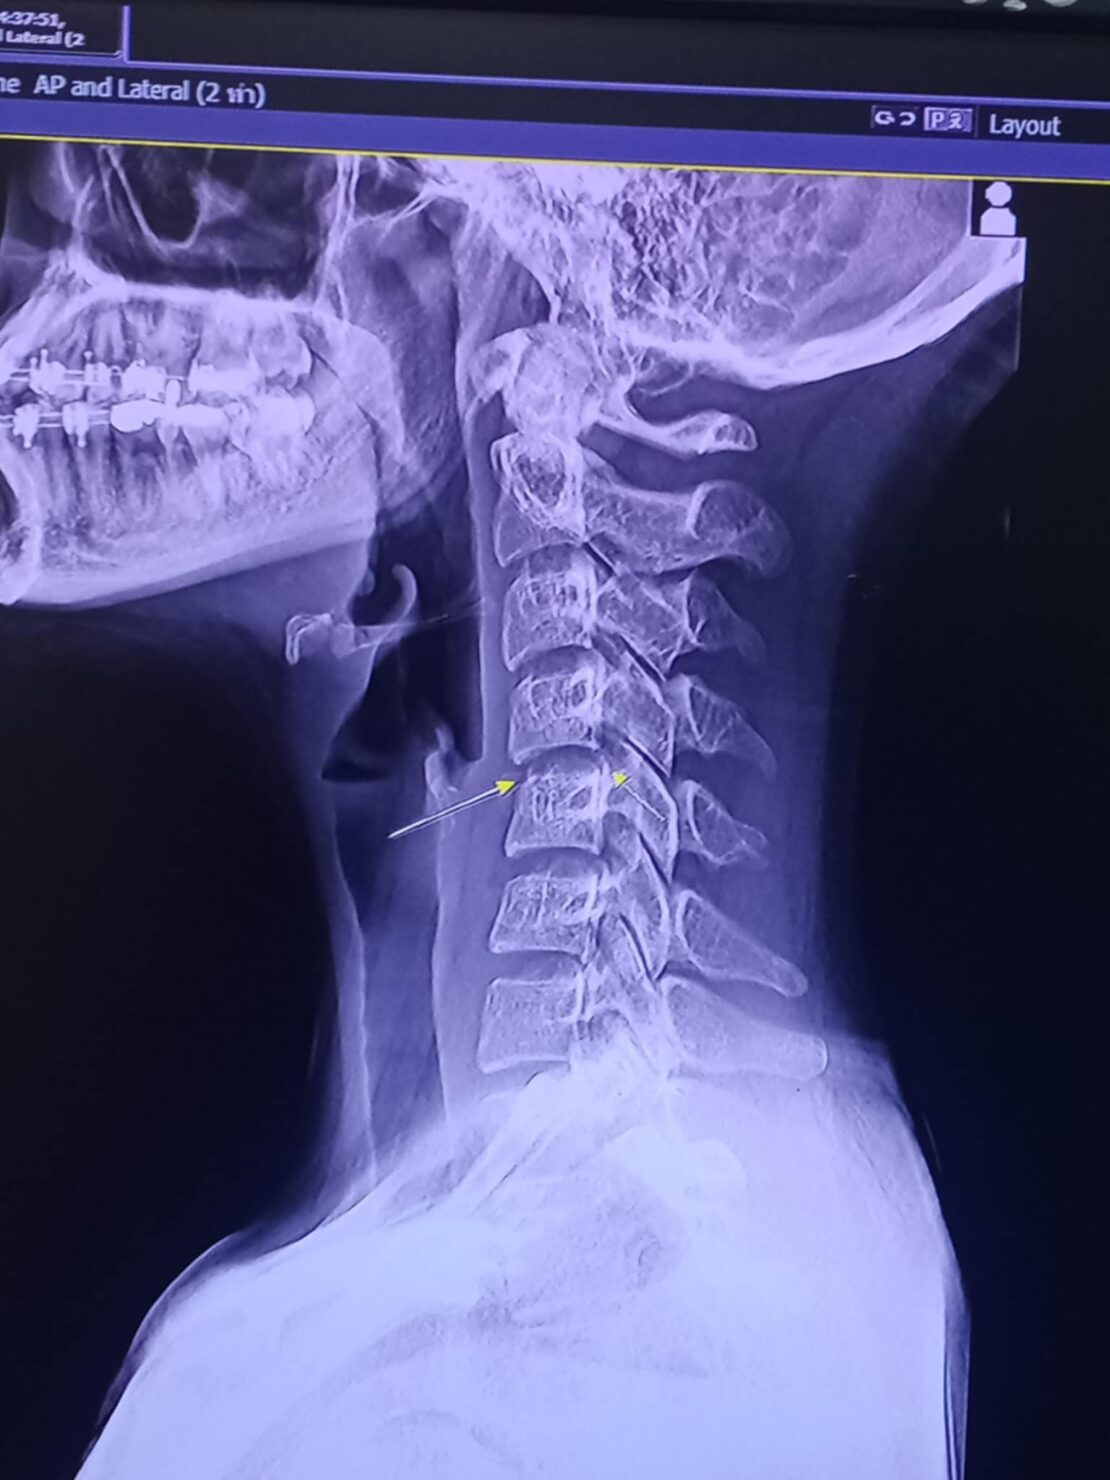

ก่อนหน้านี้ ผิง ชญาดา ได้ออกมาโพสต์ข้อความอุทาหรณ์ร้านนวดว่า “หนูไม่รู้จะเริ่มยังไงดี คนทักถามเยอะมากว่าเป็นอะไร คืองี้หนูไปนวดที่ๆหนึ่งมาค่ะ ในอุดร อาการตอนก่อนไปนวดคือหนูปวดแค่ไหล่เฉยๆค่ะ หนูไปนวดครั้งแรกอาการตอนนวดเสร็จปกติค่ะ ผ่านมา2วันหนูเริ่มปวดท้ายทอย หนูนึกว่าเป็นอาการปวดของการนวดปกติ (มีบิดคอนะคะ) หลังจากนั้นหนูกินยาระงับอาการค่ะผ่านไปอีก1สัปดาห์หนูเริ่มมีอาการชาลงแขนค่ะ ไปนวดอีกหมอคนเดิมห้องเดิม รอบนี้ (บิดคอ)อีกนะคะ ผ่านไป 2 สัปดาห์หนูเริ่มปวดตึงมากๆมากๆค่ะจนนอนหงายคว่ำไม่ได้แต่แม่หนูเป็นหมอนวดหนูเรียนนวดมาตั้งแต่เด็กๆค่ะ

เริ่มมีอาการไฟซ๊อตไปปลายนิ้วค่ะ คันมากจนอยากตัดมือทิ้ง ร้อนๆหนาวๆตลอดเวลาค่ะ ก้มแล้วร้าวลงขา ซีกขวารู้ว่าตัวเองชาก็ตอนทาโคโลนหลังจากรอบที่ 3 ที่ไปนวดค่ะ เริ่มรามไปท้อง ราวนม อาการชาเริ่มมากขึ้นเรื่อยๆค่ะ ผ่านไปอีก2อาทิตย์แขนขวาหนูเริ่มยกไม่ได้ค่ะ(อ่อนแรง) จนถึงตอนนี้ร่างกายหนู ใช้งานได้ไม่ถึง50%ค่ะ หนูมาเล่าเพราะมีคนถามมาเยอะ อยากฝากไว้เป็นอุทาหรณ์สำหรับใครที่ชอบนวดมากๆนะคะ หนูจะต้องหายค่ะ หนูทรมานมาก อยากทำงานแล้วค่ะ แต่ตอนนี้รอแค่เวลา ขอบคุณที่อ่านจนจบนะคะ”

- ผิง ชญาดา หมอเตือน อันตรายนวดบิดคอ เสี่ยงอัมพาต เส้นเลือดเลี้ยงสมองเสียหาย